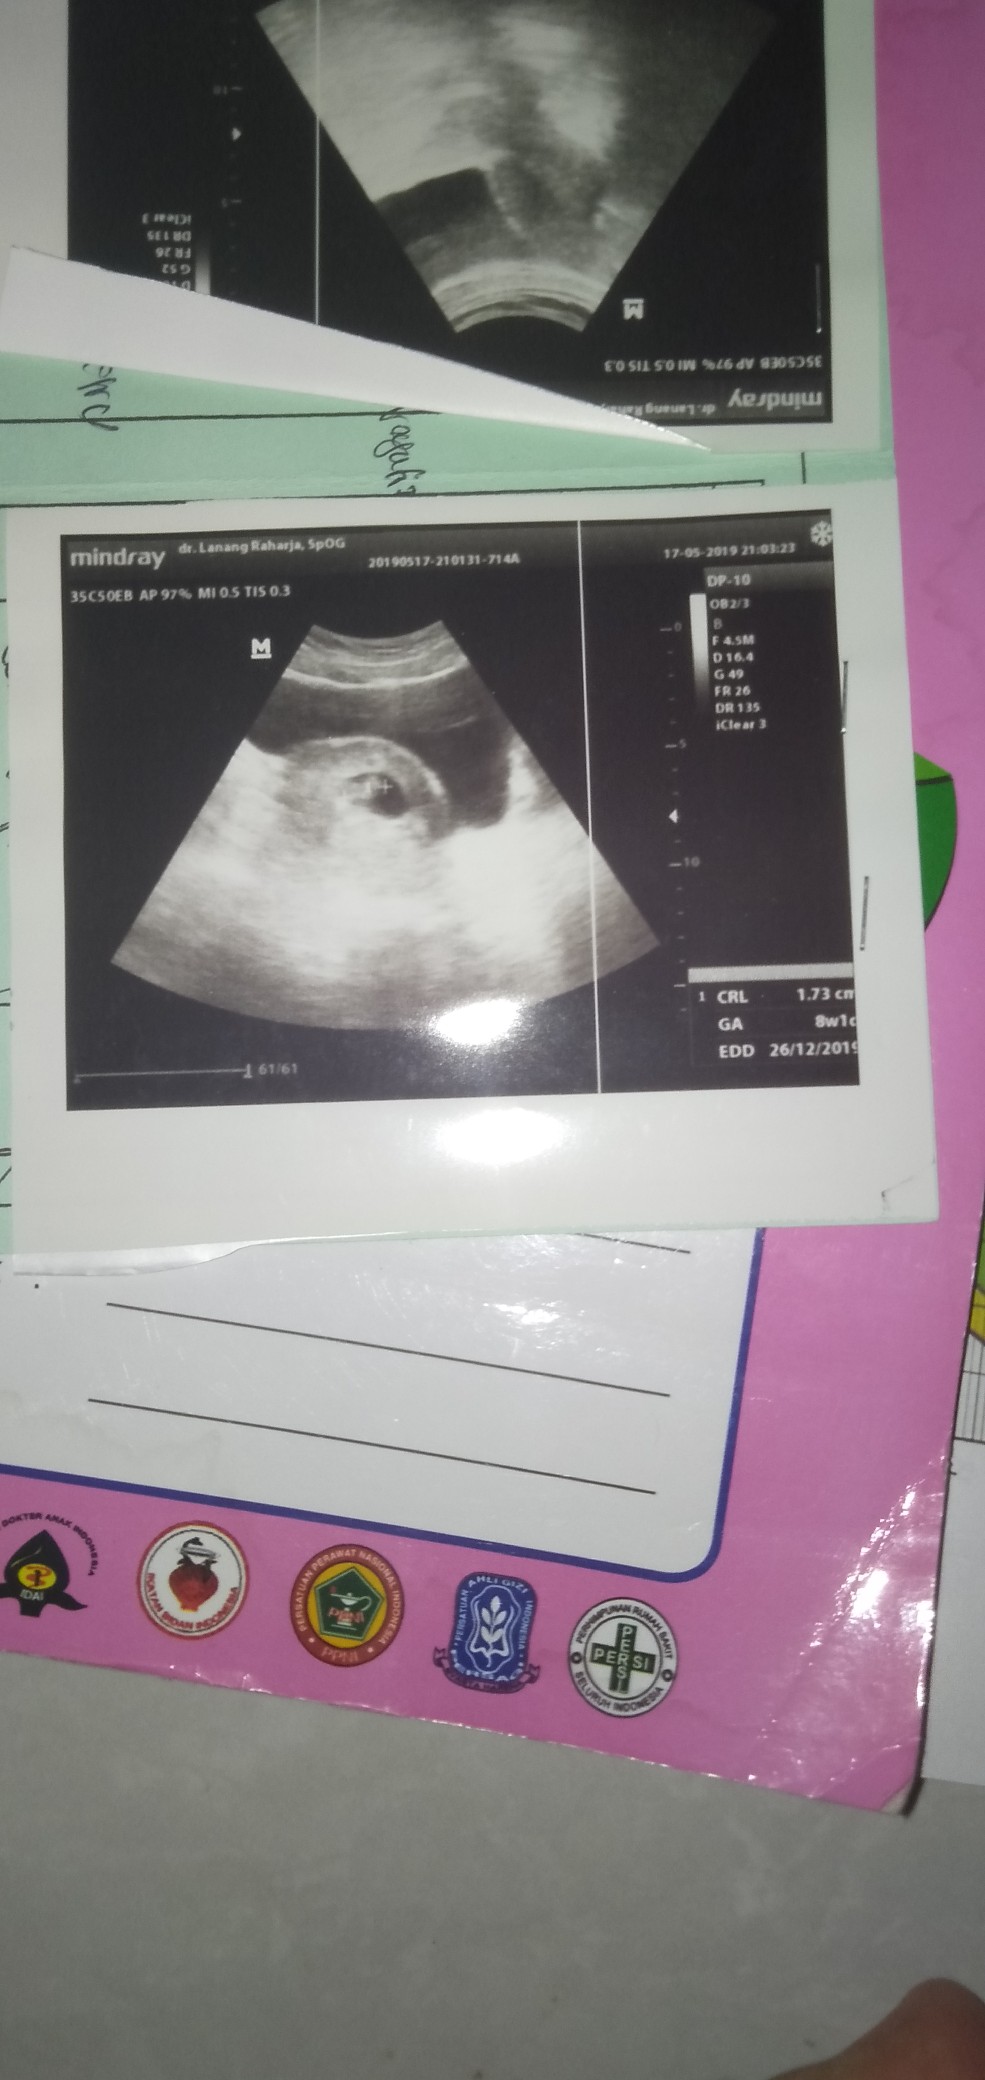

Bun apa bener kalau usg usia kehamilan 8-9 minggu itu blom ada detak jantungnya ???

biasanya udah ada.. dlu saya dr 6weeks udah keliatan

Hrs ny ud ad bun.. N ud terlihat jantung y berdetak

7w harusnya sudah ada...detek lwt USG transvaginal

Sudah bun, saya di 7 minggu sudah dnger djj.. ๐

Saya 8w udh ada detak jantungnya bund wktu d usg

Aku 8w udh ada bentuk dan jantungnya jga udh ada bun..

Usia 8week sudah terdengar detak jantung nya ko